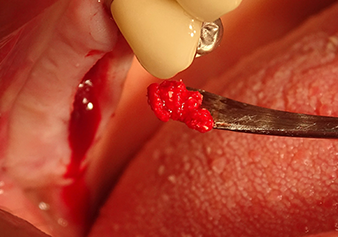

Preparazione e accrescimento della sede dell'impianto

Dopo un controllo intermedio (Fig. 4) è stata eseguita un'ulteriore fase di preparazione (Fig. 5). Lo strumento idraulico Z35P è stato utilizzato in un secondo momento per sollevare la membrana sino alla posizione desiderata (Fig. 6 e 7). In seguito alla suddetta operazione, si è proceduto ad una ulteriore preparazione piezochirurgica della sede dell'impianto conclusasi con l'applicazione della fresa e della fresa a spallamento sul diametro dell'impianto di 4,8 mm. Il materiale di rinforzo (dimensione delle particelle di ca. 0,8 - 1,6 mm) è stato introdotto sotto la membrana di Schneider prima che venisse inserito l'impianto (Fig. 8).